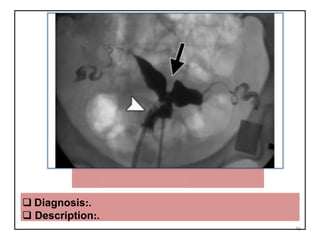

 Diagnosis:.

 Description:.